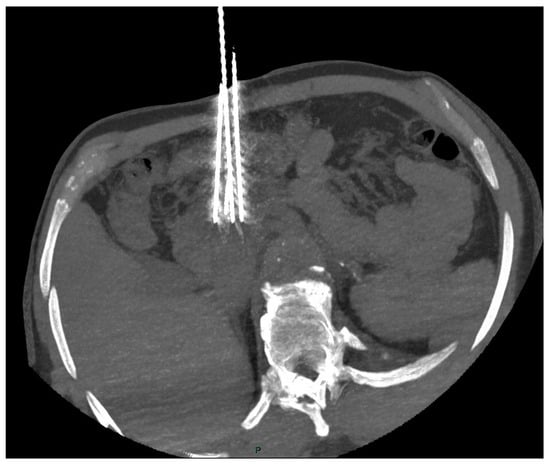

The interventional radiologist should aim for a parallel placement of the 19G electrodes (maximum angulation 10°) for an interelectrode distance of about 20 mm (15–24 mm) and for a tumor-free margin of at least 5 mm [48,49], as shown in Figure 1.

Figure 1.

CT scan shows correct placement of the 4 electrodes (19 G) at the periphery of the pancreatic head tumor (interelectrode distance < 20 mm and angulation < 10°).